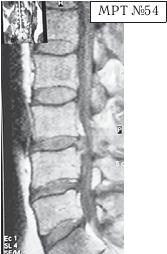

На МРТ № 54 наблюдается изменение физиологического лордоза, стеноз спинномозгового канала, грыжа межпозвонкового диска и спондилёз в сегменте LIII-LIV, ретроспондилолистез — LIV и LV.

Как правило, причина вышеупомянутых болей при таких патологиях скрывается в дугоотростчатых суставах. Дело в том, что при изменении физиологического лордоза извращается «работа» и дугоотростчатых суставов. В состоянии нормы дугоотростчатые суставы имеют дугообразную форму и расположены во фронтальной, горизонтальной и сагиттальной плоскостях в среднем под углом 45о. При развитии дегенеративнодистрофического процесса в межпозвонковом диске (снижении высоты диска, возникновении сегментарной нестабильности) происходит смещение суставных поверхностей дугоотростчатых суставов по отношению друг к другу, что в свою очередь приводит к уплощению физиологического лордоза и его кифозированию (МРТ № 55) или же формированию гиперлордоза (МРТ № 56). И в том, и в другом случае данные процессы, как правило, сопровождаются сдавлением спинномозговых корешков (что вызывает соответствующие боли). Кроме того, сами дугоотростчатые суставы хорошо иннервированы, поэтому протекание патологических процессов, с участием этих суставов, сопровождается соответствующими болевыми ощущениями.